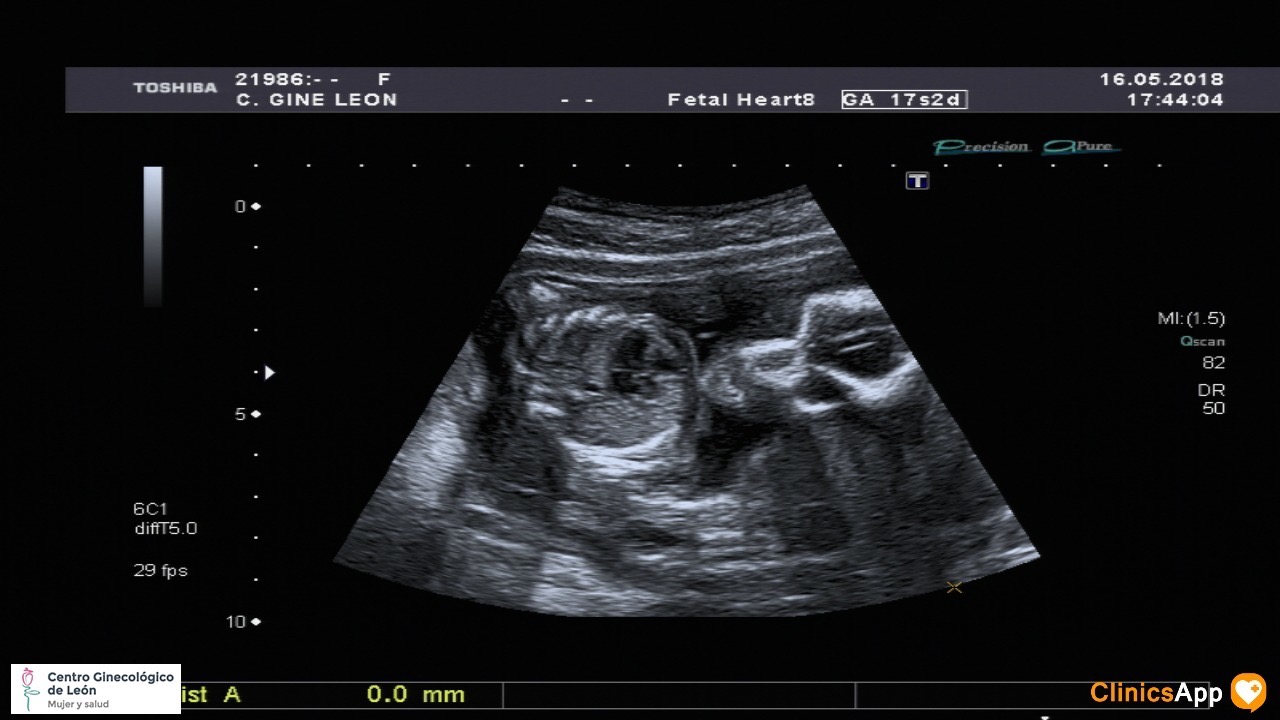

Ecografías de hoy